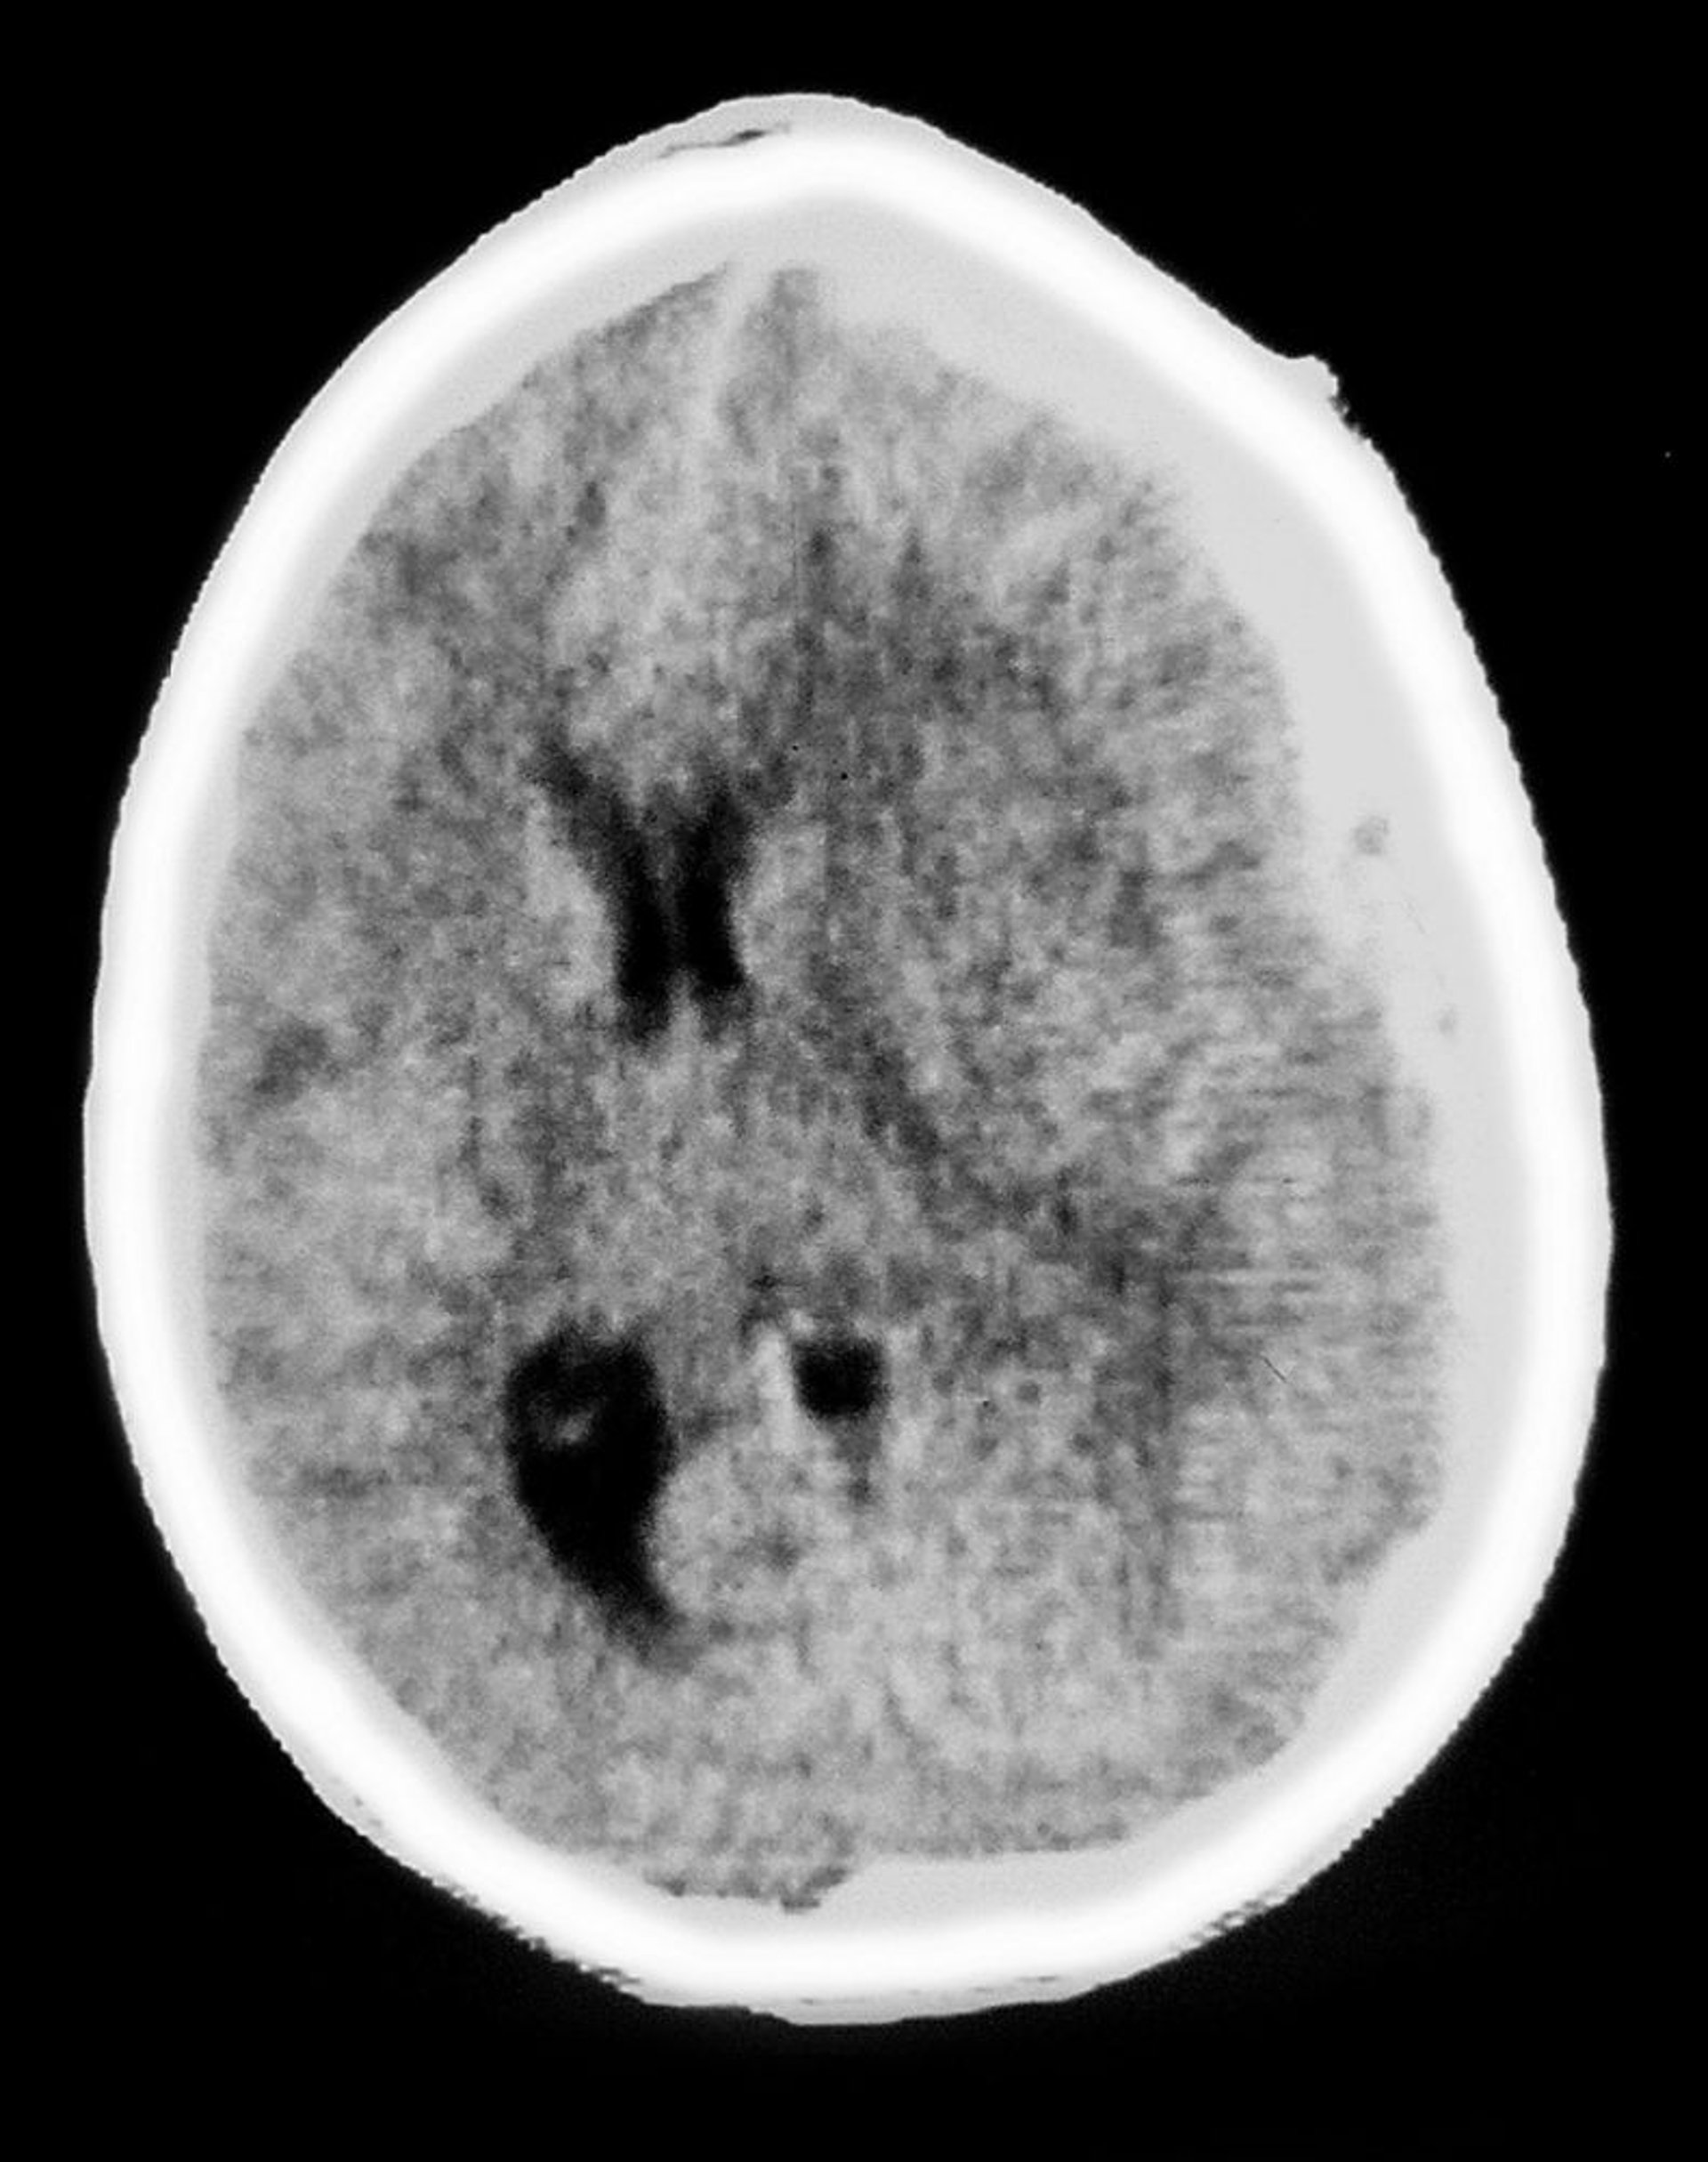

Ematoma subdurale

Questa scansione TC mostra una opacità a forma di mezzaluna sovrastante il tessuto cerebrale, caratteristica di un ematoma subdurale. Si verifica anche un effetto massa, con compressione dei ventricoli e spostamento della linea mediana.